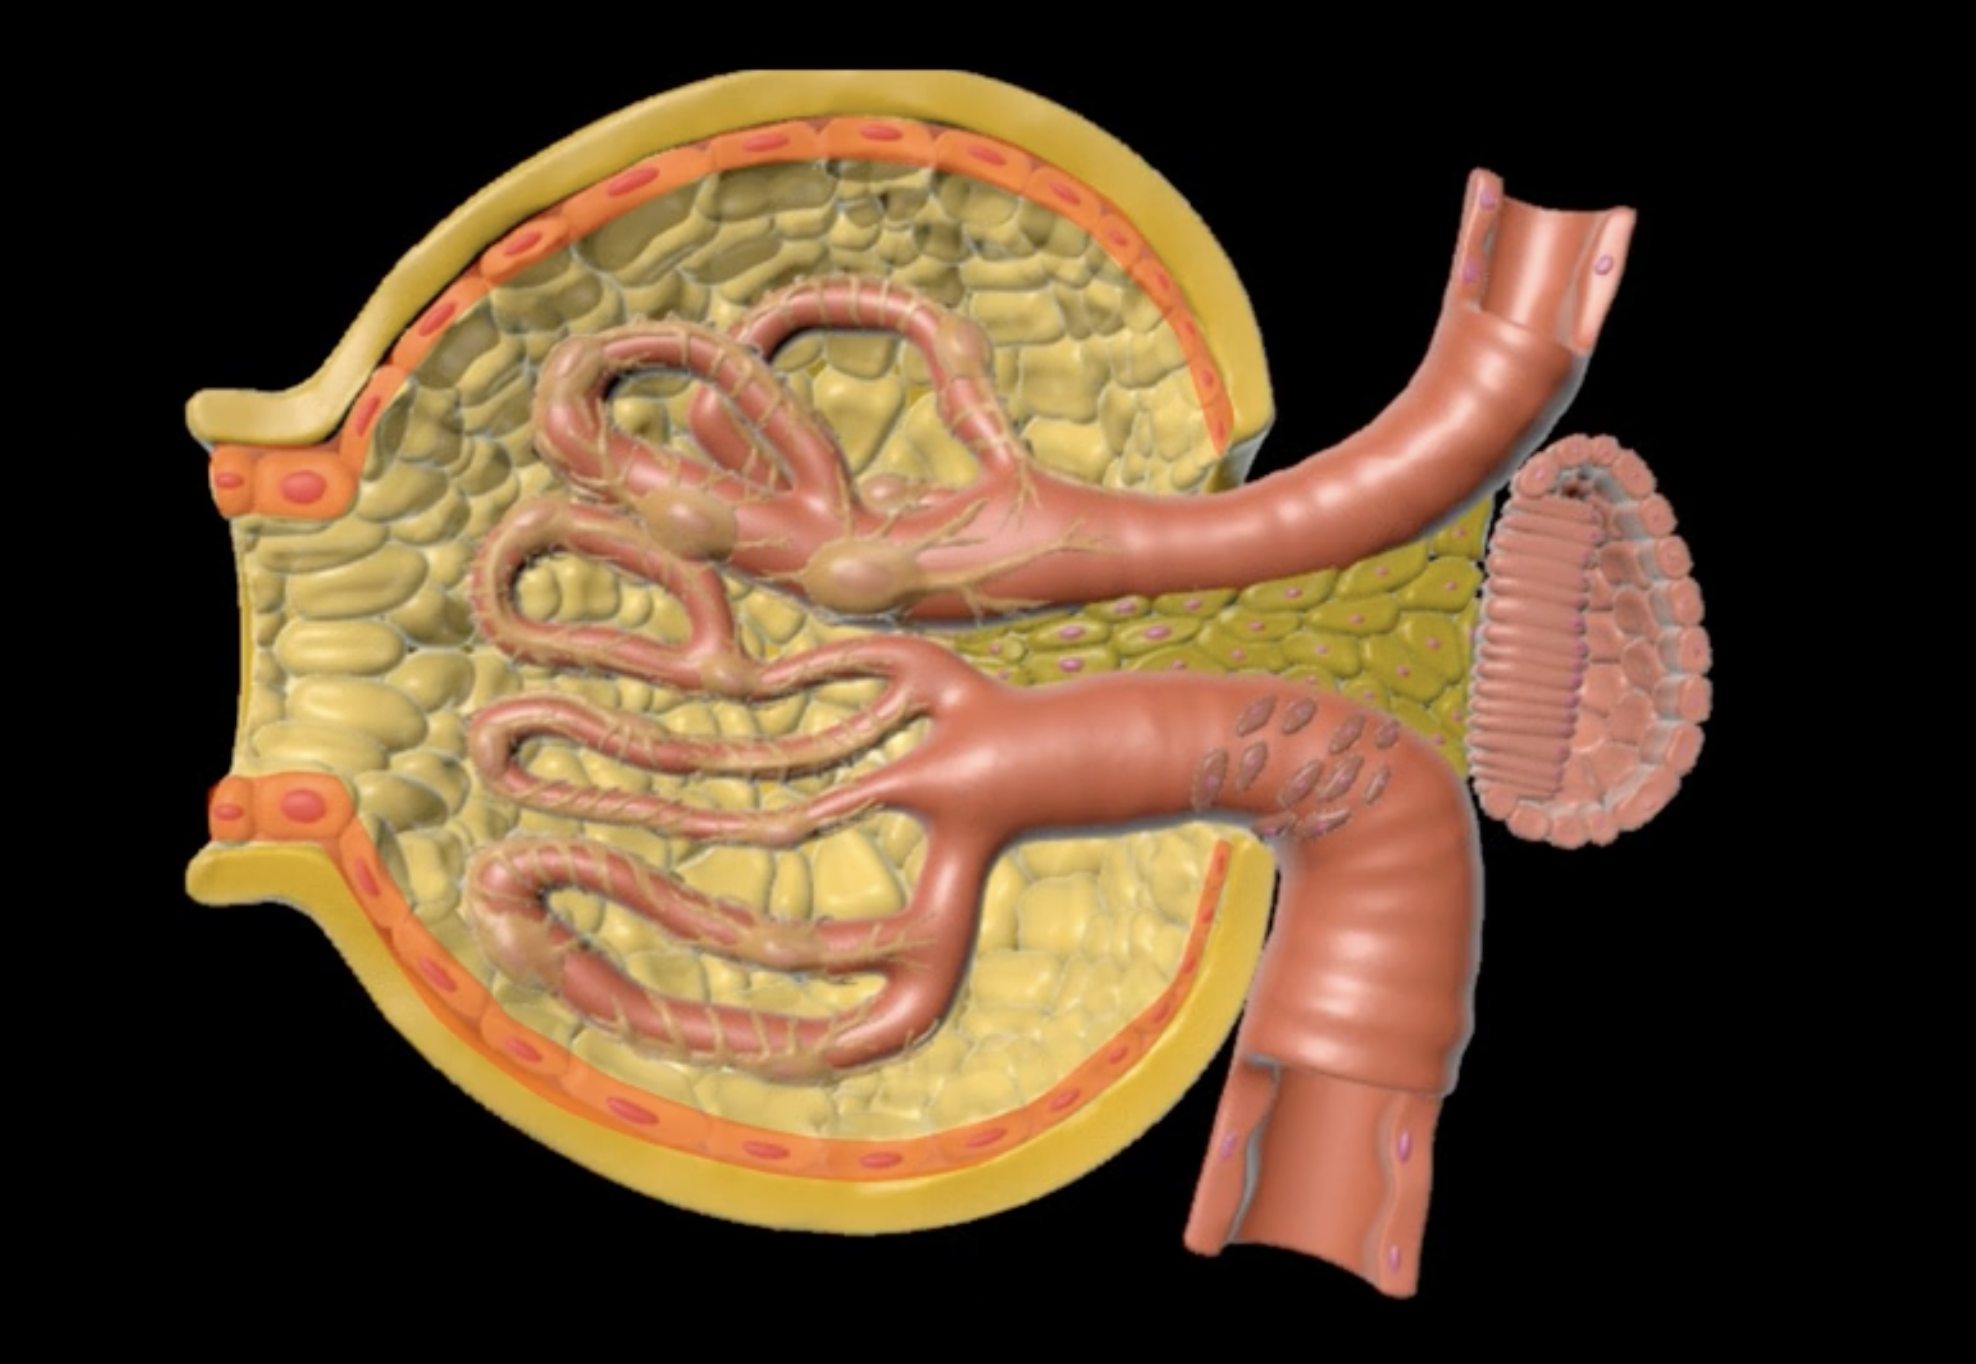

yellow: cortical nephron

blue: juxtamedullary nephron

yellow:

blue: